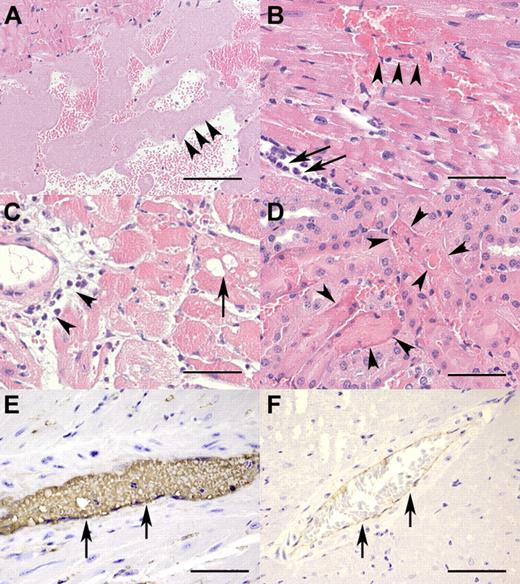

TTP-like pathohistologic changes in rhVWF-challenged animals. (A) The presence of large aggregates of platelets (arrowheads) within the left ventricle 30 minutes after TTP induction (H&E, original magnification ×100). Bar represents 200 μm. (B) Myocardial necrosis and hemorrhage (arrowheads) as well as rolling and extravasation of neutrophilic granulocytes (arrows) within the first 3 hours of TTP induction (H&E, original magnification ×400). Bar represents 50 μm. (C) Vacuolation of myocytes (arrow) and perivascular infiltration of neutrophilic granulocytes (arrowheads) within 24 hours after TTP induction (H&E, original magnification ×200). Bar represents 100 μm. (D) Renal tubular necrosis (arrowheads) characterized by loss of cellular detail, increased eosinophilia of cytoplasm, and karyopyknosis within 24 hours after TTP induction (H&E, original magnification ×400). Bar represents 50 μm. (E) Myocardial artery (arrows) immunohistochemically strongly positive for VWF 60 minutes after TTP induction (VWF immunohistochemistry, original magnification ×600). Bar represents 33 μm. (F) Myocardial artery (arrows) of an untreated control animal with minor background staining for VWF resulting from cross-reactivity of the antibody with endogenous murine VWF (VWF immunohistochemistry, original magnification ×200). Bar represents 100 μm.

Necropsy revealed that macroscopic lesions were restricted to the heart and consisted of multifocal, well-delineated, dark-red discolorations of the myocardium 1 to 2 mm in diameter (acute myocardial hemorrhage and necrosis). On day 1, moderate to severe myocardial necrosis was accompanied by infiltration of large numbers of neutrophilic granulocytes, hemorrhage, and fibrin precipitation. These lesions were more pronounced in the proximal half of the heart (Figure 2C). On day 3, hemorrhage and myocardial lesions were observed with a similar distribution pattern as on day 1. In addition to the neutrophilic granulocytes, macrophages and lymphocytes were present and proliferation of fibroblasts was evident. On day 14, interstitial fibrosis was the predominant pathologic feature. VWF-specific immunohistochemical staining showed its presence in areas of hemorrhage and necrosis, with the overall staining intensity being weaker on day 3 than on day 1 (data not shown).

Minimal, acute tubular necrosis in the kidneys was seen in the majority of rhVWF-treated animals on day 1 (Figure 2D) and in a few animals on day 3. On day 14, no differences were noted between control and rhVWF-treated animals. The incidence and severity grade of regenerative tubuli were higher in the rhVWF-treated group than in untreated ADAMTS13 KO mice. The indices were also higher on day 3 than on day 1 (data not shown). Notably, no lesions were identified in the brain of rhVWF-treated animals.

These hematologic findings were consistent with pathologic findings. Macroscopic lesions were seen as early as 6 hours after rhVWF treatment and were again restricted to acute myocardial hemorrhage and necrosis. Histopathologic changes included ventricular and vascular platelet aggregations (hyaline [micro-] thrombi) in animals killed between 15 minutes and 3 hours after rhVWF administration (Figure 2A). Furthermore, myocardial lesions were recorded as early as 15 minutes after administration of rhVWF and consisted of necrosis of individual myocytes and hemorrhage. After 3 hours, infiltration of neutrophilic granulocytes along with hemorrhage of increased severity became evident (Figure 2B). Minimal, peracute tubular necrosis in the kidneys was seen 1 hour after treatment in a few animals. However, after 9 hours, lesions were observed in the majority of animals in the rhVWF-treatment group (data not shown). Immunohistochemistry revealed intense VWF staining of hemorrhagic and necrotic areas in the myocardium as well as more intense intravascular staining at all time points within the first 9 hours (Figure 2E), whereas nontreated animals showed only minimal staining (Figure 2F).